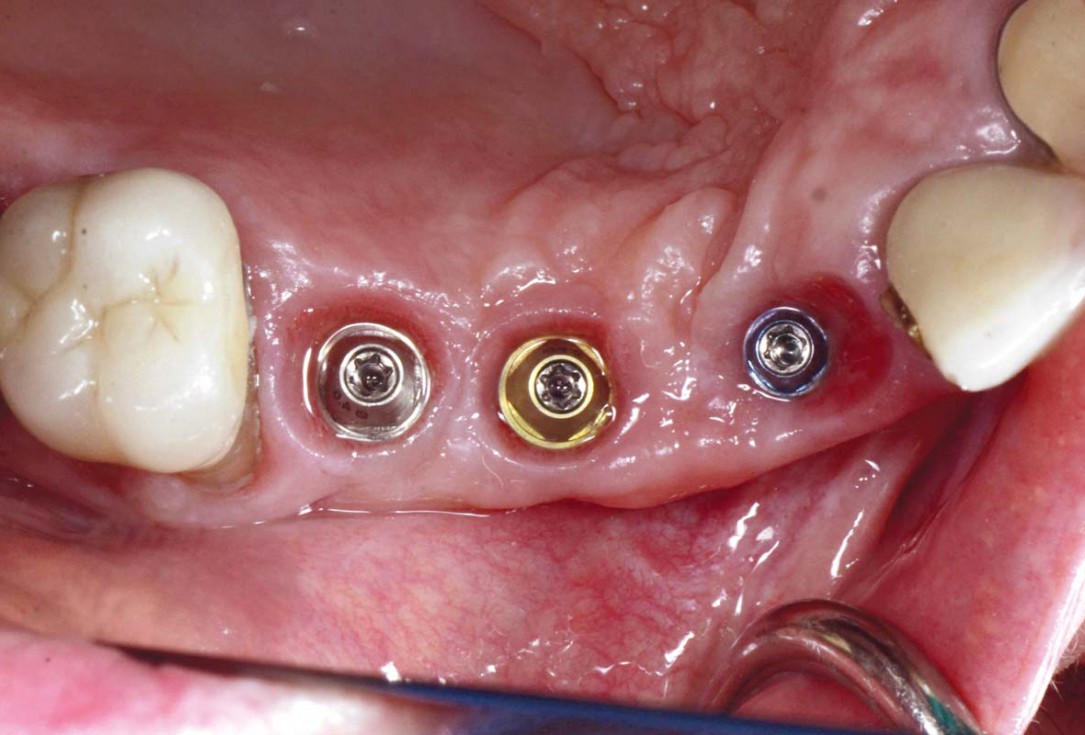

Bone defect in area 11-21 due to two lost implants (periimplantitis) after 15 years of function